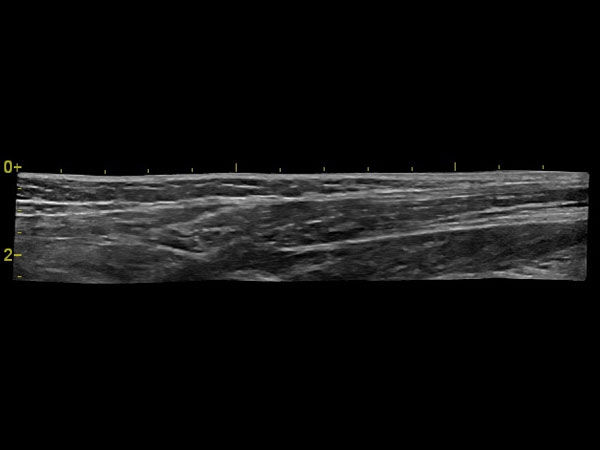

• ангиология;

Панорамное сканирование:

Да

IMT (Intima Media thickness):